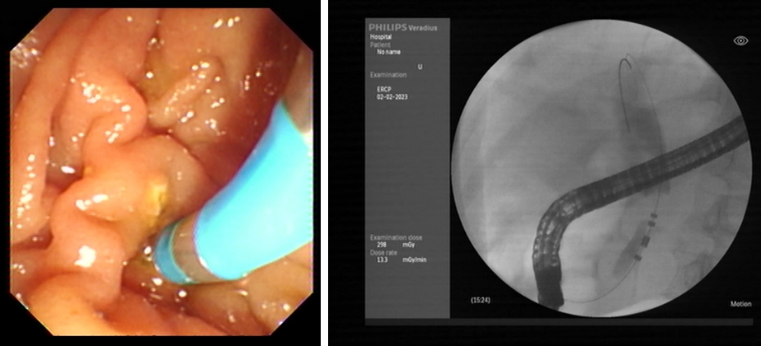

据了解,首例手术患者为一例局部晚期胰腺癌病人,失去了根治性手术的机会,同时因梗阻性黄疸且伴有糖尿病等基础疾病,一般状况较差,难以耐受化疗,常规治疗手段无法有效开展。针对该患者的病情特点,西安交通大学副校长吕毅教授、一附院肝胆外科仵正主任、胆胰内镜外科孙昊主任、胰腺外科王铮主任等经过仔细充分的术前讨论,与患者家属进行了多次医患沟通,最终决定为该患者实施内镜下脉冲电场肿瘤消融术。经过充分的术前准备,在医院麻醉手术部、介入手术室等团队的支持配合下,由肝胆外科孙昊主任医师、杨雪副主任医师、李宇主治医师、任冯刚博士等为该患者成功实施了ERCP+内镜下脉冲电场肿瘤消融术+胆道支架植入术。

值得一提的是,得益于脉冲电场能量高度密集,脉冲消融过程仅用时约100秒,消融区平均温度40℃,手术过程安全可控,术后患者生命体征平稳,胆汁引流通畅,经过恢复于2月8日顺利出院。

本次手术采用了具有完全自主知识产权的国产高性能医疗器械。脉冲电场消融导管为吕毅教授团队自主研发、通过脉凝医疗实施转化的EndoPulse HPB阵列式脉冲电场消融导管,该导管头端由多支环形电极构成阵列,可以满足不同类型病变的应用需求。脉冲电场能量平台为赛诺微医疗科技与吕毅教授团队合作研发的Dophi®陡脉冲治疗仪。